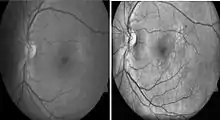

Diabetic retinopathy

Diabetic retinopathy is a disease of the retina that is diagnosed predominantly by fundoscopic images. Diabetic patients in industrialised countries generally undergo regular screening for the condition. Imaging is used to recognize early signs of abnormal retinal blood vessels. Manual analysis of these images can be time-consuming and unreliable.[75][76] CAD has been employed to enhance the accuracy, sensitivity, and specificity of automated detection method. The use of some CAD systems to replace human graders can be safe and cost effective.[76]

Histogram Equalization Sample Image. Left: Normal gray-scale fundoscopic image. Right: Post-histogram equalization processing.[79]

Histogram equalization is useful in enhancing contrast within an image.[80] This technique is used to increase local contrast. At the end of the processing, areas that were dark in the input image would be brightened, greatly enhancing the contrast among the features present in the area. On the other hand, brighter areas in the input image would remain bright or be reduced in brightness to equalize with the other areas in the image. Besides vessel segmentation, other features related to diabetic retinopathy can be further separated by using this pre-processing technique. Microaneurysm and hemorrhages are red lesions, whereas exudates are yellow spots. Increasing contrast between these two groups allow better visualization of lesions on images. With this technique, 2014 review found that 10 out of the 14 recently (since 2011) published primary research.[77]